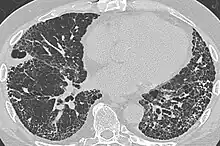

| CT scan of a patient with UIP. There is interstitial thickening, architectural distortion, honeycombing and bronchiectasis. | |

UIP may be diagnosed by a radiologist using computed tomography (CT) scan of the chest, or by a pathologist using tissue obtained by a lung biopsy.

Radiologically, the main feature required for a confident diagnosis of UIP is honeycomb change in the periphery and the lower portions (bases) of the lungs.[3]

On high-resolution computed tomography (HRCT), the following categories, depending on imaging findings, have been recommended by a collaborative effort by the American Thoracic Society, European Respiratory Society, Japanese Respiratory Society, and the Latin American Thoracic Society:[4]

- UIP pattern:[4]

- Honeycombing, with or without peripheral traction bronchiectasis; or bronchiolectasis (dilatation of the terminal bronchioles)[5]

- Predominantly subpleural and basal

- Often heterogenous distribution, being occasionally diffuse, and may be asymmetrical

There may be superimposed CT features such as mild ground-glass opacity, reticular pattern and pulmonary ossification.